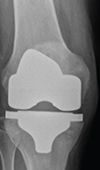

Massive Patellar Tendon Ossification: Excision and Simultaneous Total Knee Replacement

Tendon ossification has a multifactorial aetiology. We present a case of a massive ossification within the substance of patellar tendon. A 79-years-ol... Read more